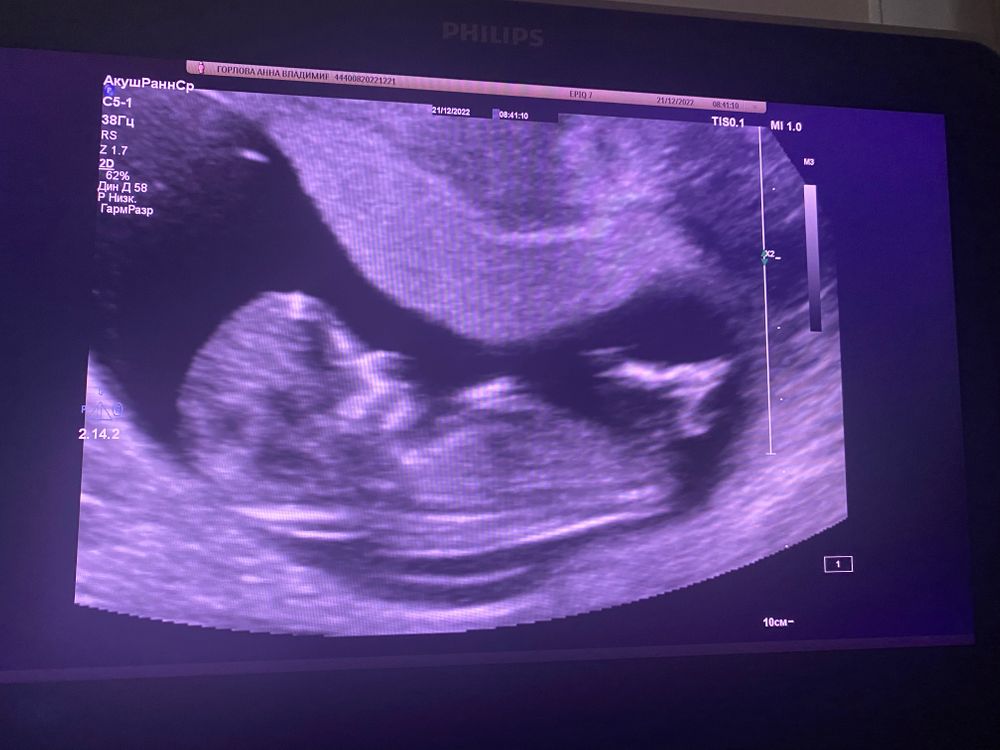

На первом скрининге по такому расположению малыша не понять, кто будет. Надо фото сбоку, чтобы был виден половой бугорок.

Annie, в общем-то, я думаю, что у вас мальчик. По форме лба на скрининге, по расположению хориона (плаценты) на этом узи.. но посмотрим, время покажет)

По форме лба похож на мальчика малыш, полового бугорка не видно чётко, а сердцебиение сходится далеко не у всех. У меня не сошлось. На 1 скрининге узистка тоже девочку предположила. На 2 я не спрашивала. Была уверена , что девочка. Но, врач сама сказала, что мальчик. Так что если чётко не видно бугорок, вилами по воде всё это. И даже с бугорками ошибаются)

Ирина, ну лоб у нас у всех такой большой, у дочки тоже так было)) вот половой бугорок Изображение